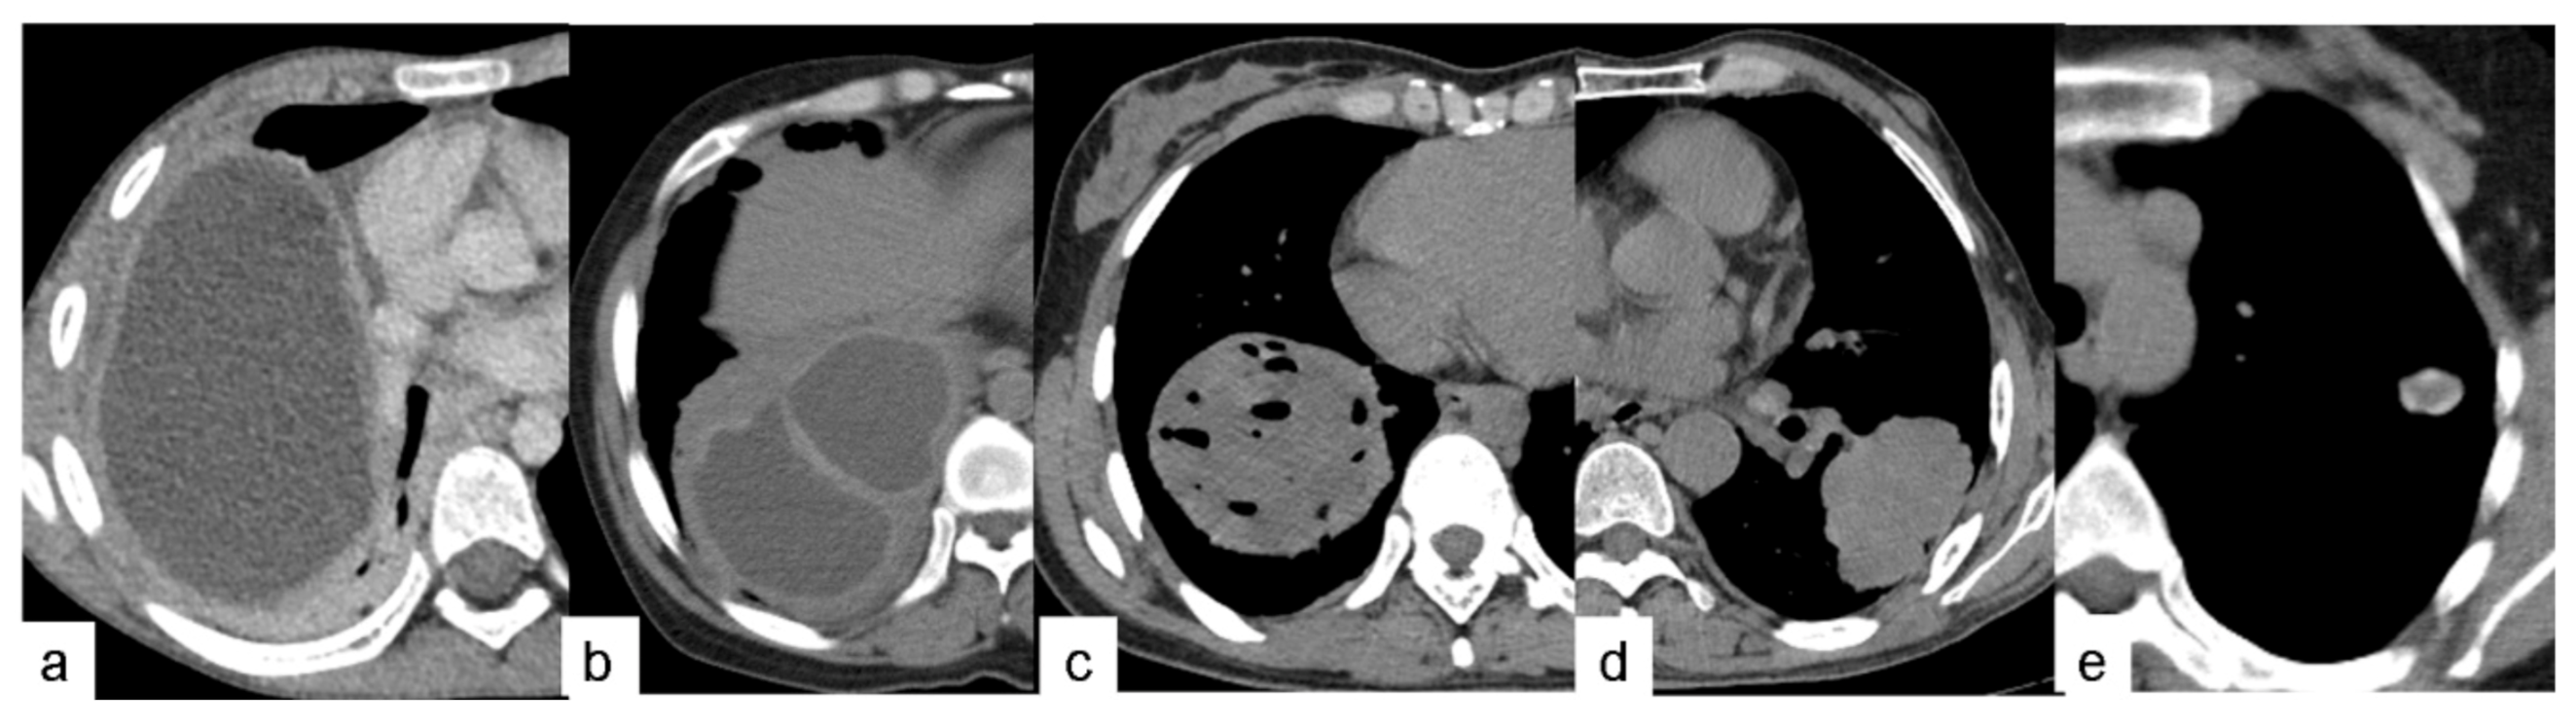

The preoperative CT findings of the 46 PCE lesions were classified according to the WHO ultrasound classification of hepatic cystic echinococcosis. There were no cases of CL lesions found. These lesions demonstrate unclear development on CT and have a thin cyst wall and contain fluid similar to water. There were 19 cases with CE1 lesions. These lesions have a round or oval shape with a thin, well-defined, and smooth cyst wall of relatively high density, containing water-like fluid, and there is potentially a gap between the inner and outer cyst walls, resembling a “double-wall” (Figure 1a). CE1-type cysts and cyst walls were not enhanced by the contrast agent. There were two cases of CE2 lesions. These lesions are reported as two or more relatively small cysts, which have a representative “cyst-in-cyst” appearance (Figure 1b). There were 21 cases of CE3 lesions, of which 19 cases were CE3a and 2 cases were CE3b. These lesions have a complicated appearance following the rupture of hydatid cysts. Gas had entered between the internal and external cysts in two cases, resembling a “crescent” shape (Figure 2c). In another case, the inner and outer cysts had ruptured, and the internal cyst attached itself to the wall of the external cyst without collapsing, which resulted in a “double-crescent” shape (Figure 2d,e). In yet another case, the cyst wall had collapsed, curled, and wrinkled and was floating in cystic fluid, taking the appearance of a “ribbon” shape (Figure 2f). In 17 cases, the cyst wall laceration connected with the bronchi, and the cyst contents had been discharged. Additionally, gas had entered the cystic cavity, resulting in either a “floating lotus” appearance when the cavity contained more cystic fluid (7 cases, Figure 2g) or a “stone-emerging-from-water” appearance when the cavity contained less fluid (10 cases, Figure 2h). Coronal and sagittal MSCT MPR (multi-planner reformatted) images showed that these lesions were strongly connected to the bronchi. There was one case of a CE4 lesion that had a solid appearance that was not enhanced with contrast agent on CT (Figure 3). One case had adhesion of a cystic echinococcosis lesion in the lower lobe of the right lung, which penetrated through the diaphragm (Figure 4). Additionally, there were three cases of CE5 lesions. These lesions are characterized by thick, calcified cystic walls and visible, irregular strip-like and arc-shaped calcifications (Figure 1e).

Figure 1. For the 46 PCE lesions included in this study, thin-section CT findings were classified according to the WHO ultrasound classification of hepatic cystic echinococcosis: (a) Type of CE1 with single-cyst lesions. (b) Type of CE2 with multi-cyst lesions. (c) Type of CE3a with internal cyst rupture lesions. (d) Type of CE4 with consolidation lesions. (e) Type of CE5 with calcified lesions.